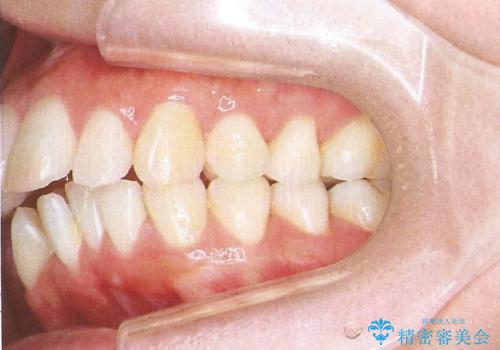

裏側装置で出っ歯の矯正治療

- 出っ歯を目立たない器具で治療したいとのことで来院されました。

上顎の前から4番目の歯を両側抜歯して、上下裏側の装置で前歯を引っ込める計画としました。

裏側からの矯正であったため、表側に比べて少し治療期間を要しました。